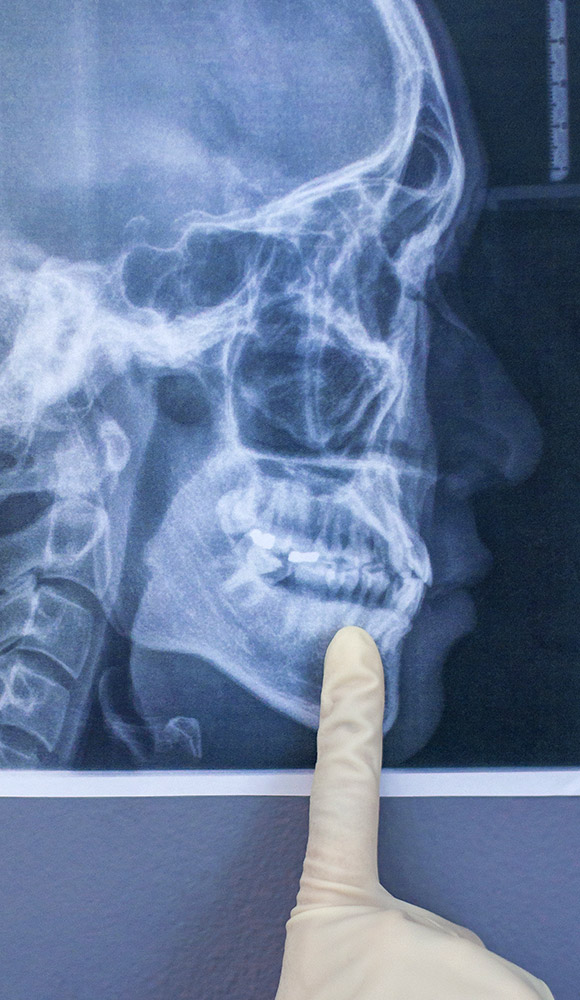

Teleradiogram

Teleradiogram je profilni rendgenski snimak glave neophodan u ortodontskoj dijagnostici i planiranju terapije. Omogućava analizu rasta, razvoja i položaja vilica, kao i međusobnih odnosa zuba i viličnih kostiju. Ova dijagnostička metoda je ključna za precizno određivanje ortodontskih aparata i postizanje optimalnih terapijskih rezultata.